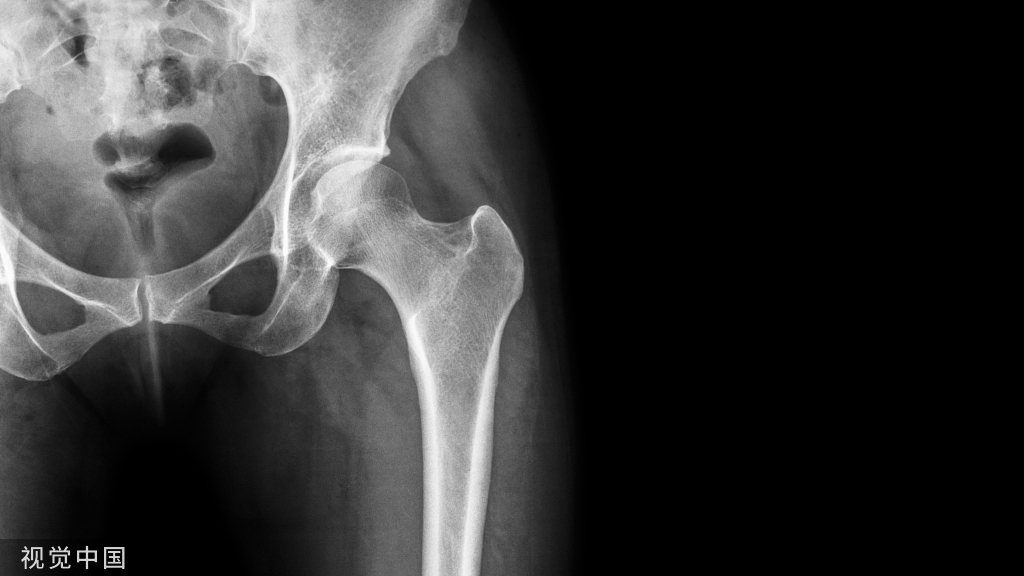

最新版:中国髋、膝关节置换日间手术围手术期管理专家共识!

结合前期髋、膝关节置换日间手术的经验,遵循循证医学原则,根据GRADE 等方法(表 1~2)对证据质量进行评价分级,最终整理编辑完成此项专家共识,供广大骨科医生在临床工作中参考和应用。